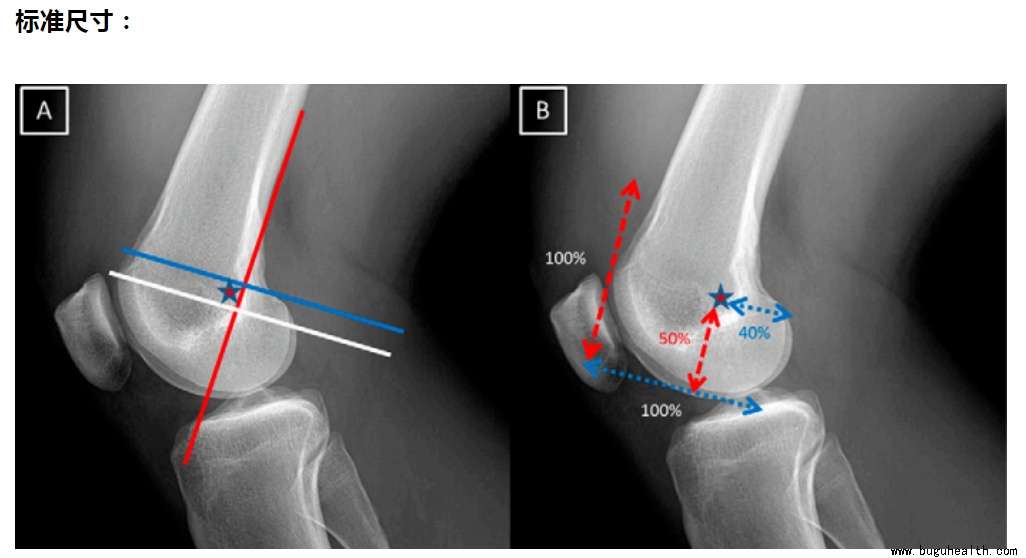

MPFL 股骨侧定位:

内侧髌股韧带(MPFL)股骨端的起源是基于 Schottle 点上,Schottle 点(星)是股骨后方皮质的切线前方 1 mm(红色线),股骨髁上缘垂线远端 2.5 毫米(白色线),和 Blumensaat 线上后方的近端垂直线(蓝线)。

标准尺寸:

当股骨内侧髁被认为是水平距离 100%,髌骨上关节缘至股骨髁远端边界是纵向距离 100%,MPFL 附着点位于股骨内侧髁上距离后方 40%,远端 50%,前方 60% 的位置(星)。